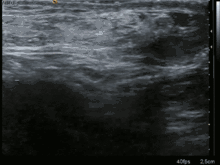

بعد الاشتباه في التشخيص، غالبا ما يتم تأكيد ذلك عن طريق التصوير الطبي. وعندما يتم التقييم بالموجات فوق الصوتية أو بالتصوير المقطعي أو التصوير بالرنين المغناطيسي، يكون الفرق الرئيسي في تشخيص الفتق الأربي غير المباشر هو التمايز عن الأورام الشحمية في الحبلي المنوي، حيث أن كلا منهما يمكن أن يحتوي على دهون فقط وقد تمتد على طول القناة الأربية في كيس الصفن.[18]